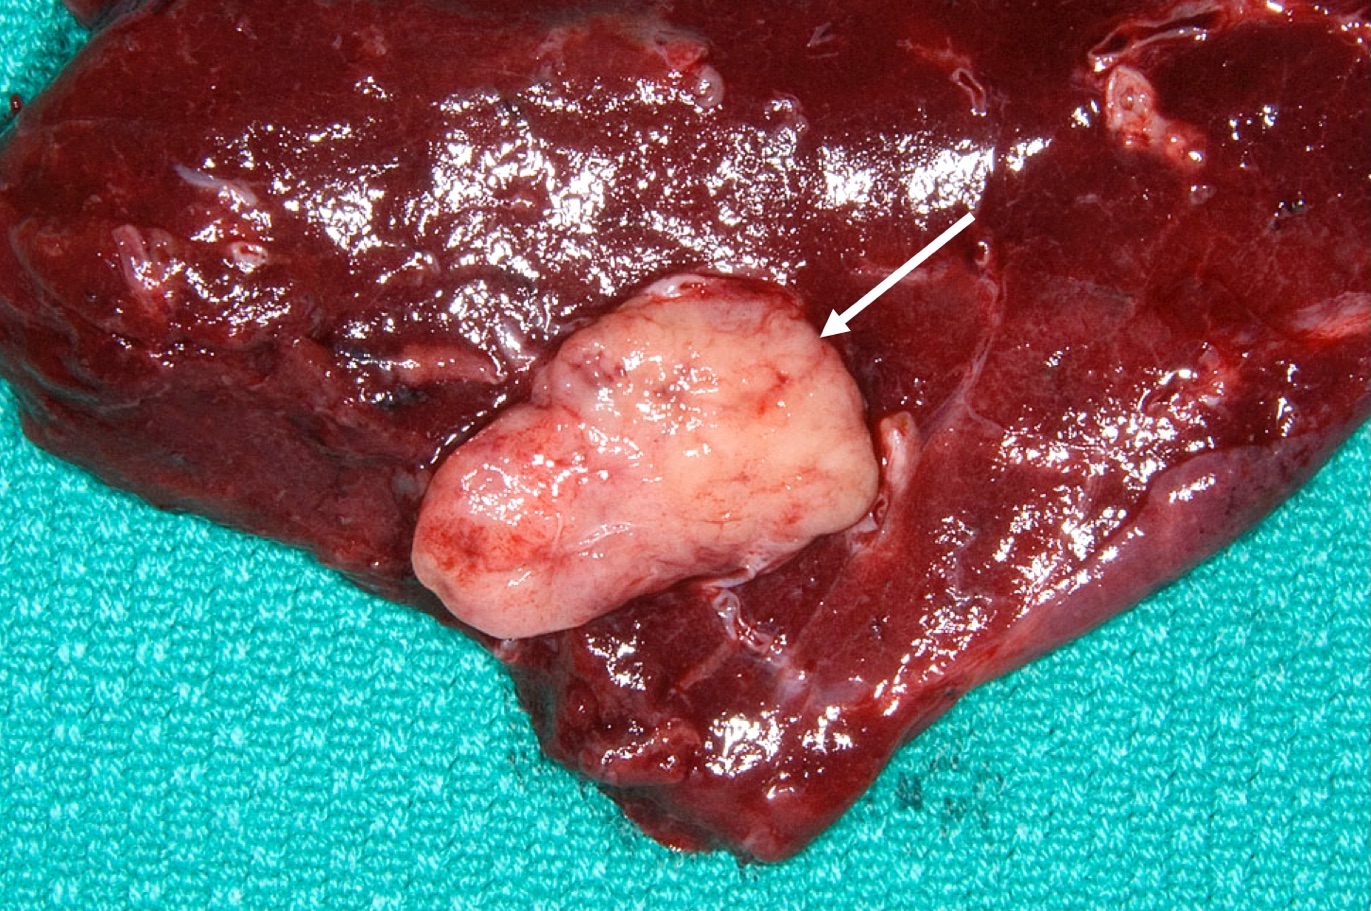

Gross description

- Well circumscribed, round to oval tan colored tumors

- Localization

- Frequently in bronchial lumen, sessile or pedunculated with partial or complete obstruction of the lumen

- Peripheral tumors may not be evidently located in airways

- Size range: 0.5 - 9.5 cm

- Reference: Lung Cancer Int 2015;2015:545601

Gross images